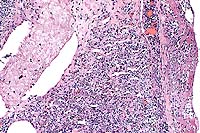

Conference Note: Disseminated histoplasmosis causes a variety of clinicopathologic findings. In dogs, hematologic abnormalities often include a leukocytosis resulting from neutrophilia and monocytosis. There may be a left shift. As was seen in this case, a nonregenerative anemia is common, due both to chronic inflammatory disease and to replacement of normal bone marrow elements by Histoplasma-laden histiocytes. Thrombocytopenia has been a variable feature in dogs.

Serum chemistry changes indicating cholestatic liver disease are often found, including increases in serum alkaline phosphatase activity and conjugated bilirubin levels. Serum albumin is often decreased. Alanine aminotransferase is only occasionally increased, due to the infiltrative rather than hepatocellular nature of the disease. Serum globulin concentrations may be normal or increased.

In cats, clinicopathologic changes are reported to be similar to those in dogs, and can include nonregenerative anemia, degenerative left shift, neutropenia, hypoalbuminemia, and hyperglobulinemia.

The wide spread dissemination of the H. capsulatum organism throughout the body resulted in these additional lesions:

3. Severe, chronic, multifocal to coalescing granulomatous

hepatitis with intralesional yeasts (Histoplasma capsulatum).

4. Severe, chronic, diffuse granulomatous lymphadenitis with intralesional

yeasts (Histoplasma capsulatum).

5. Moderate, chronic, multifocal granulomatous pneumonia with

intralesional yeasts (Histoplasma capsulatum).

6. Severe, chronic, multifocal to coalescing granulomatous splenitis

with intralesional yeasts (Histoplasma capsulatum).